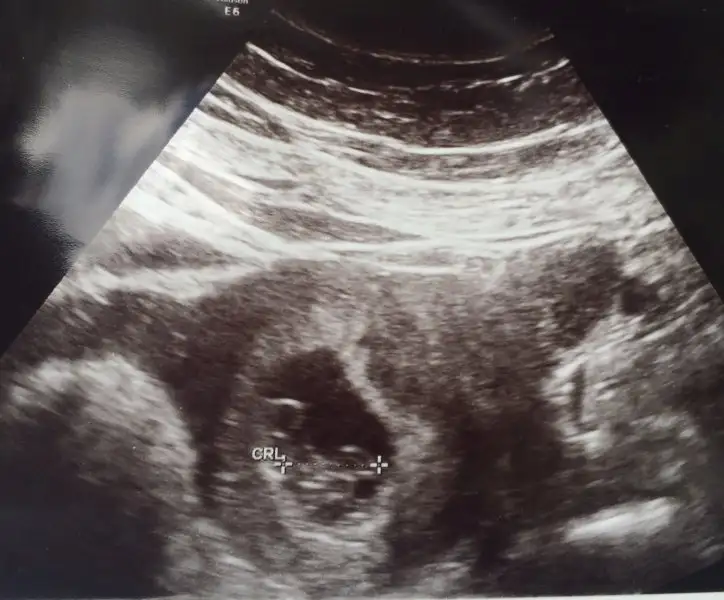

Kızlar merhaba benim bebişim için de cinsiyet tahmininde bulunabilir misiniz? Karından ultrason 6+1 ve 7+5 :)

• 6+1.webp

6+1.webp

13 KB · Görüntüleme: 217

• 7+5.webp

7+5.webp

14,1 KB · Görüntüleme: 249